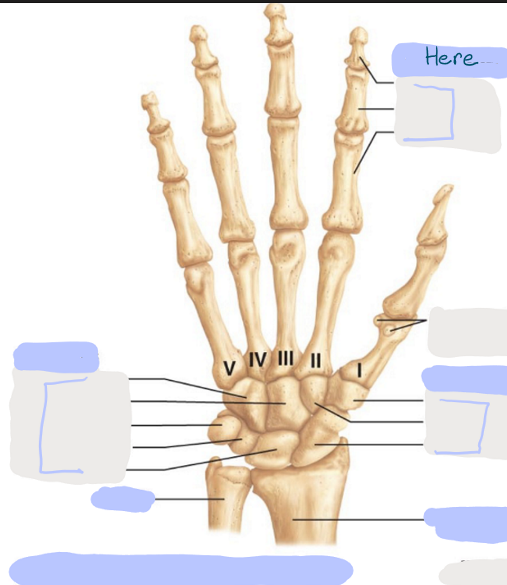

What is this picture of?

Anterior View of the Right Hand

What is here?

Where is the Ulna?

What is here?

Where is the Radius?

What is here?

Where are some of the Carpals?

What is here?

Where are some of the Carpals?

What is here?

Where are the Phalanges?